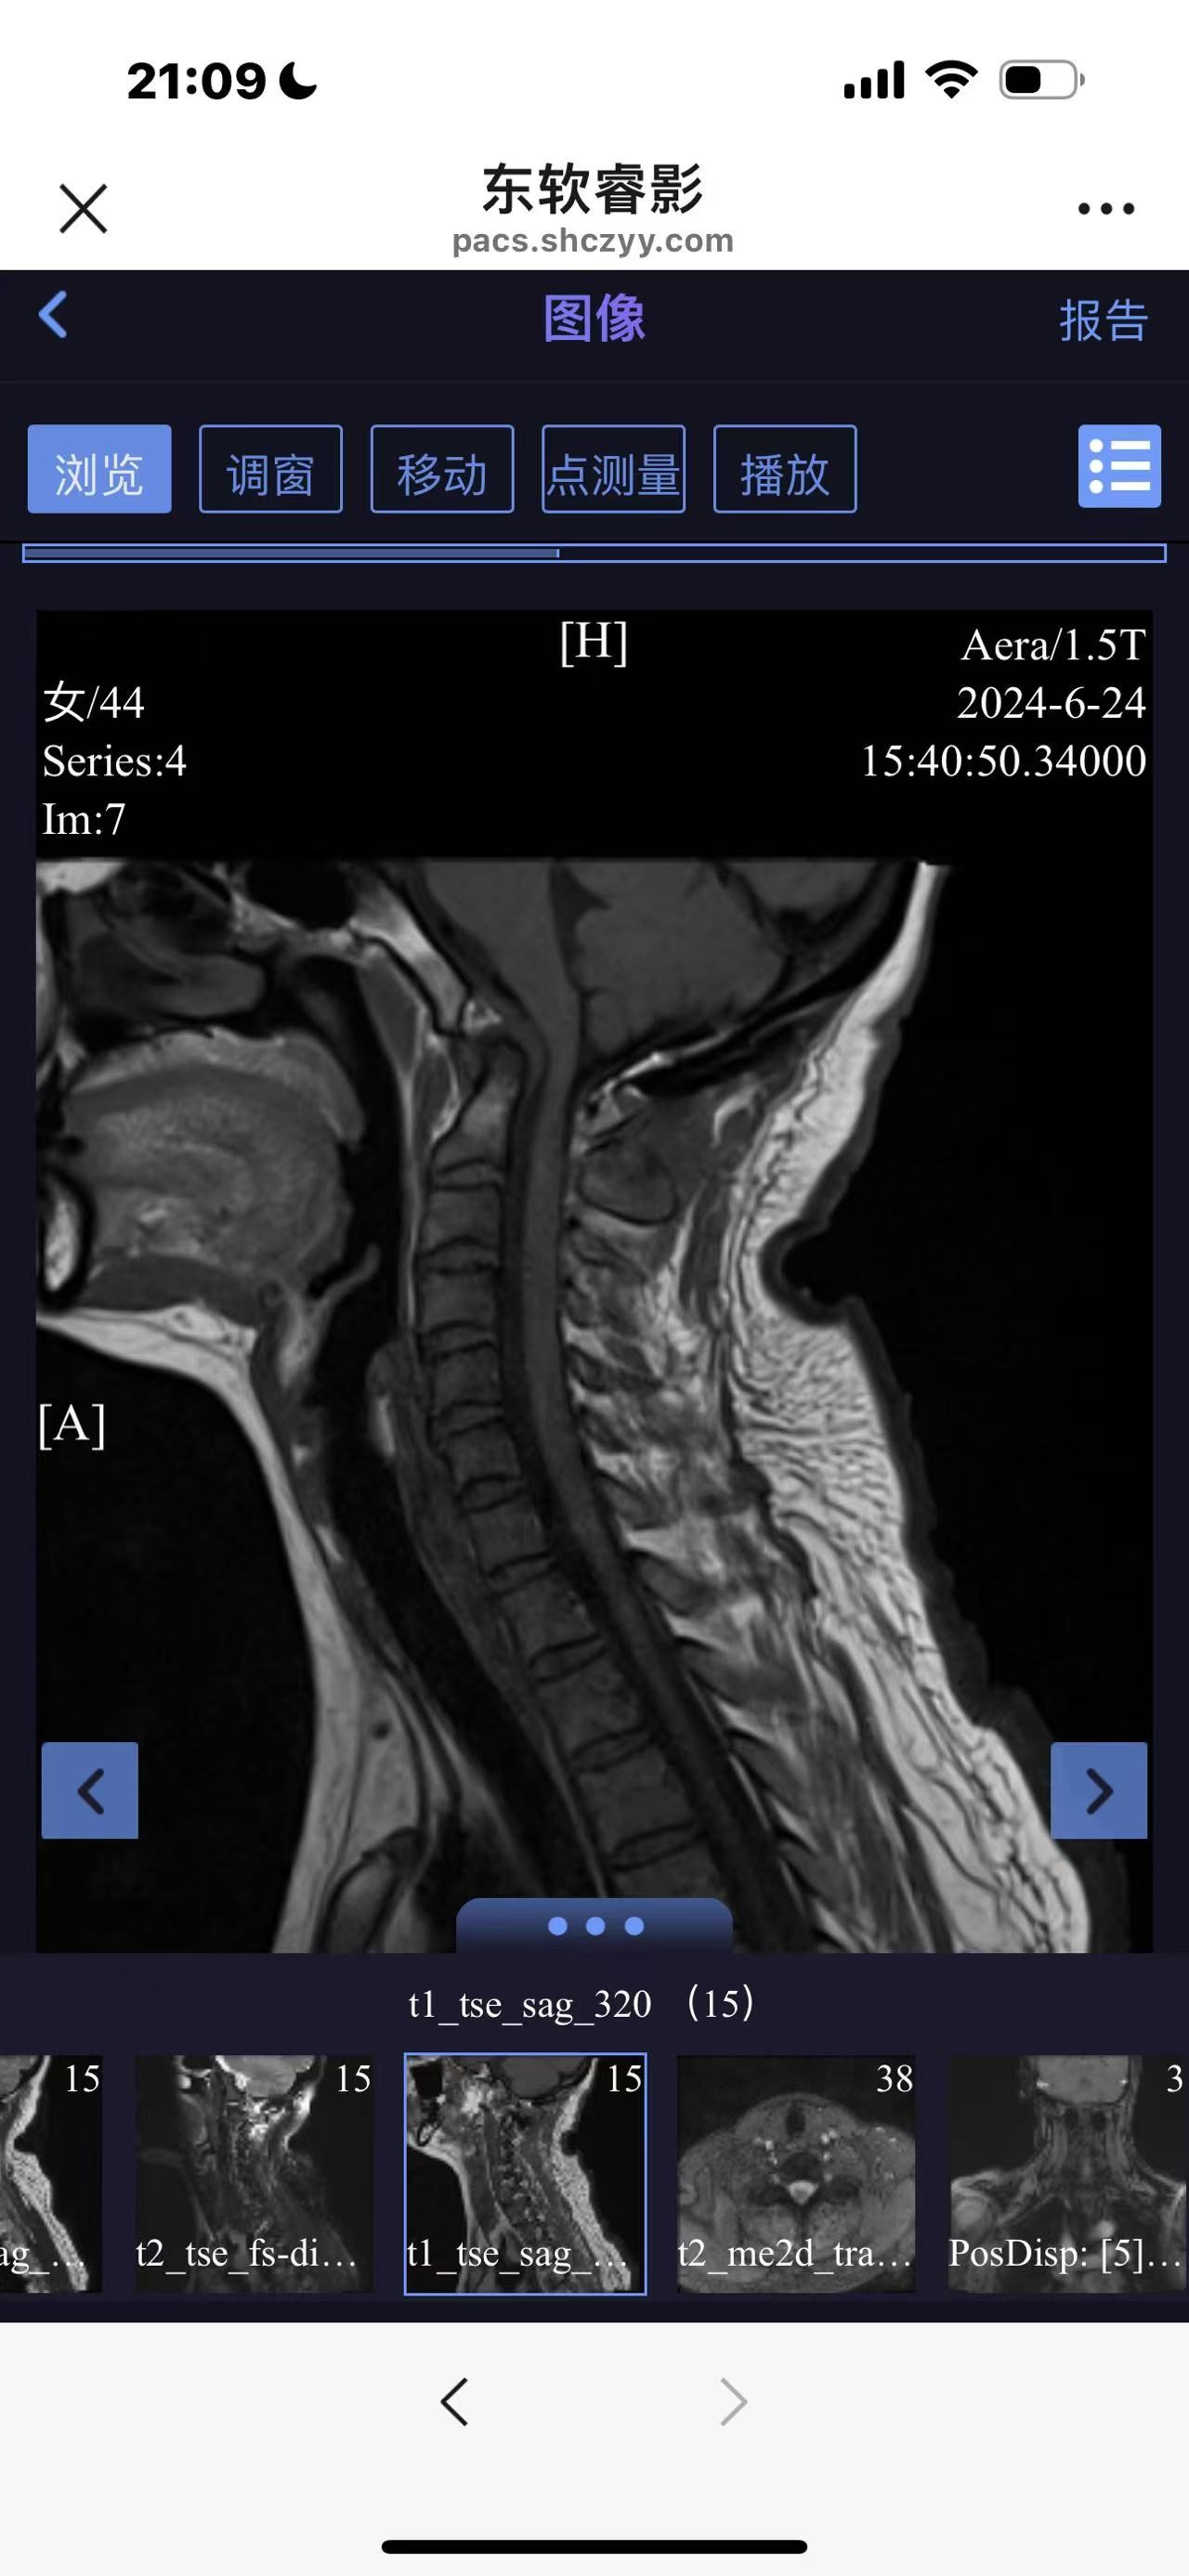

• 诊断:寰枢椎脱位

• 日期:2024.06

• 医院:上海长征医院

• 术后状况:没有复位

• 术后影像: